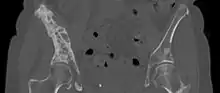

CT Scan

A CT scan can detect bone metastases before becoming symptomatic in patients diagnosed with tumors with risk of spread to the bones. Even sclerotic bone metastases are generally less radiodense than enostoses, and it has been suggested that bone metastasis should be the favored diagnosis between the two for bone lesions lower than a cutoff of 1060 Hounsfield units (HU).[10] If a biopsy is indicated, a CT scan is important for localizing the prospective sample tissue.[13]